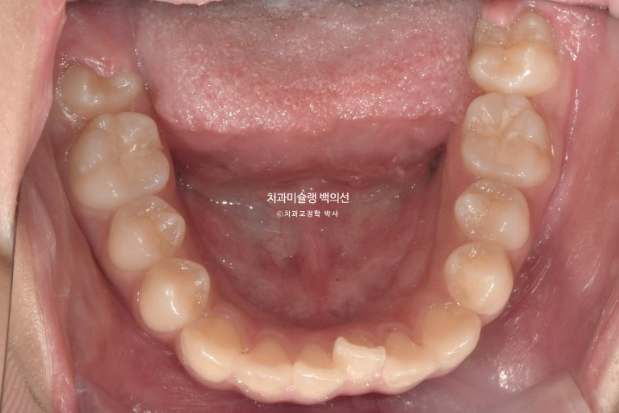

25.09

중심선은 잘 맞으며 앞니 교합은 적절합니다.

어금니 교합은 1급이고 좋습니다.

25.10~25.09

그 사이 두번째 큰어금니까지 모두 나와 잘 배열되었습니다.